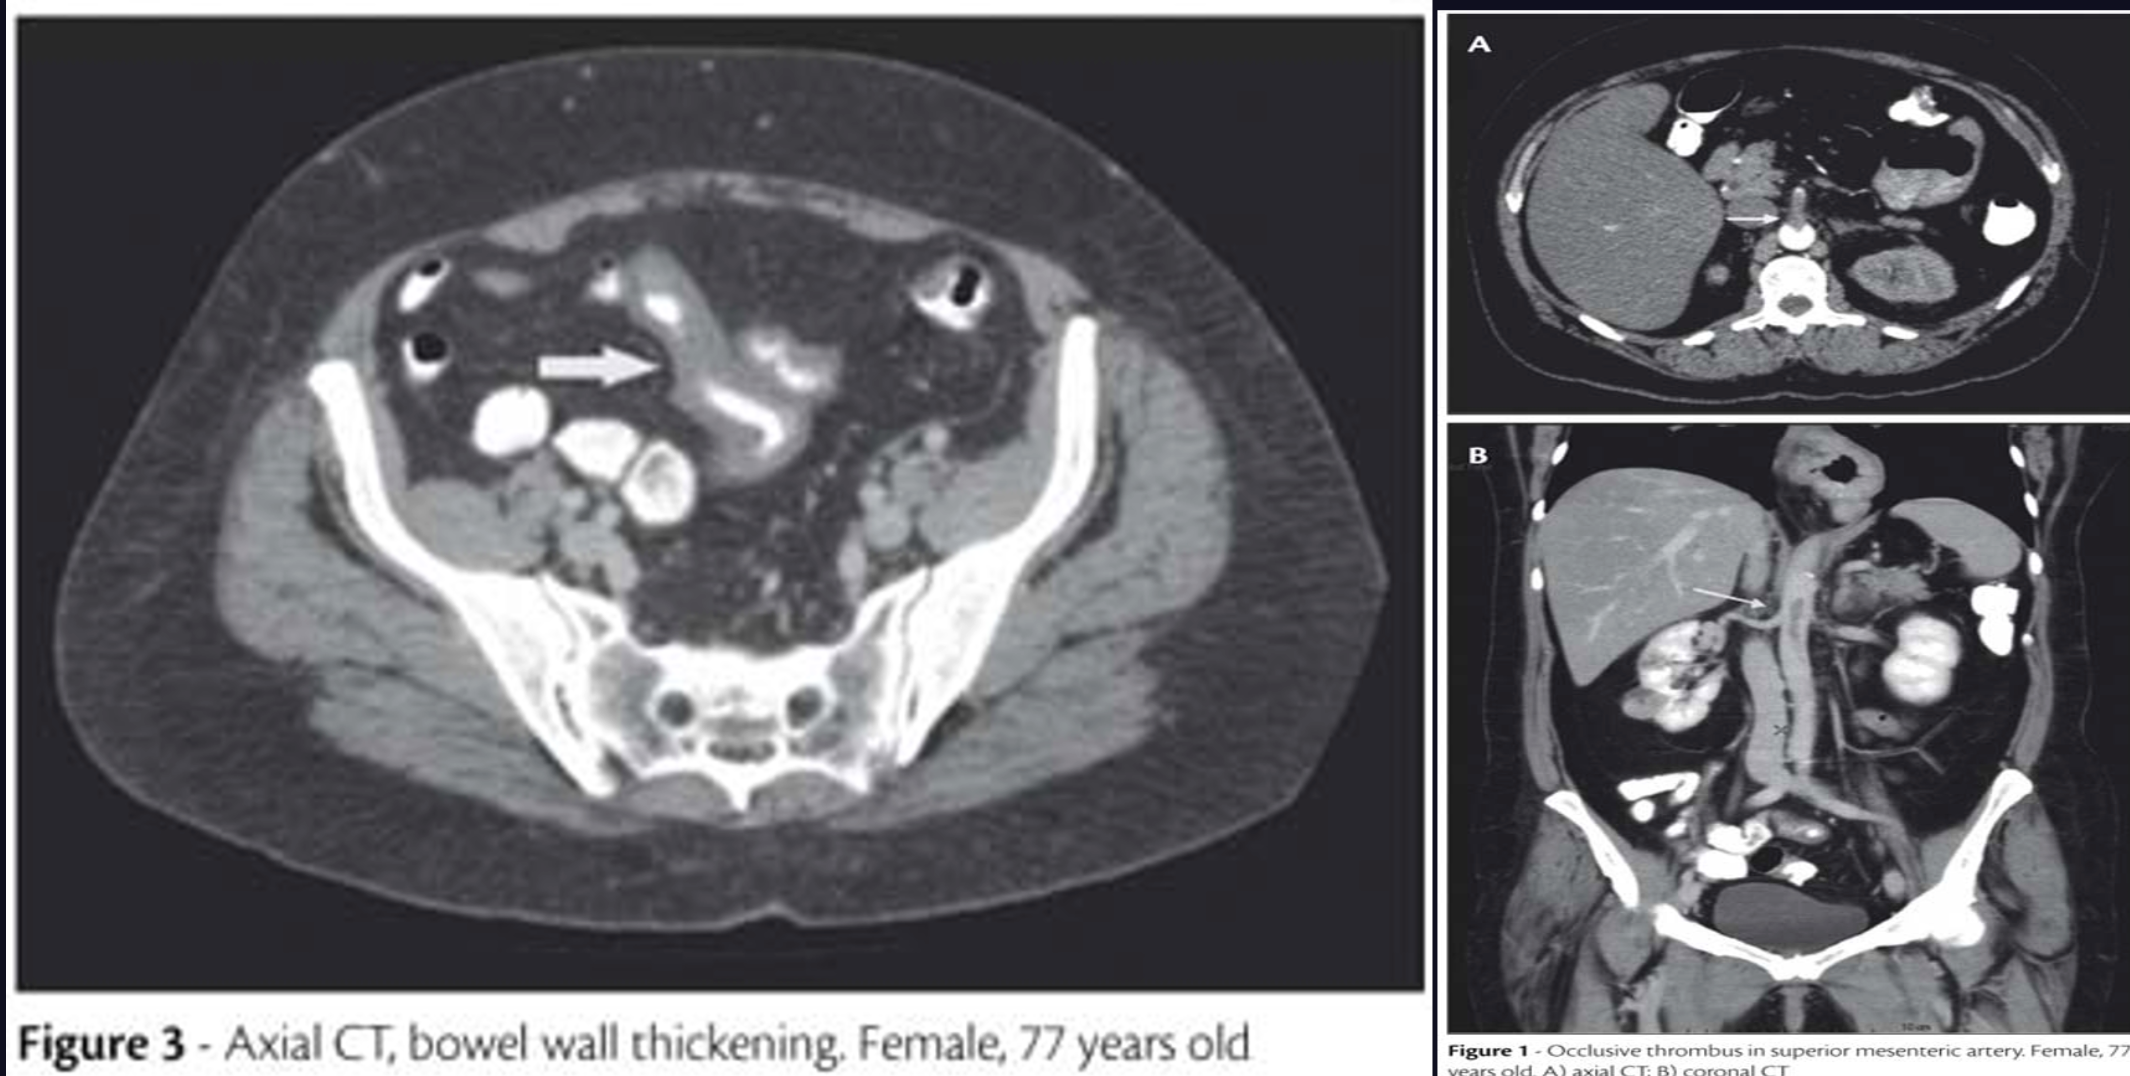

- CT angiography

- Exclude other pathology

- Assess mesenteric vasculature, intestine & its mesentery

- Test of choice for acute mesenteric venous thrombosis